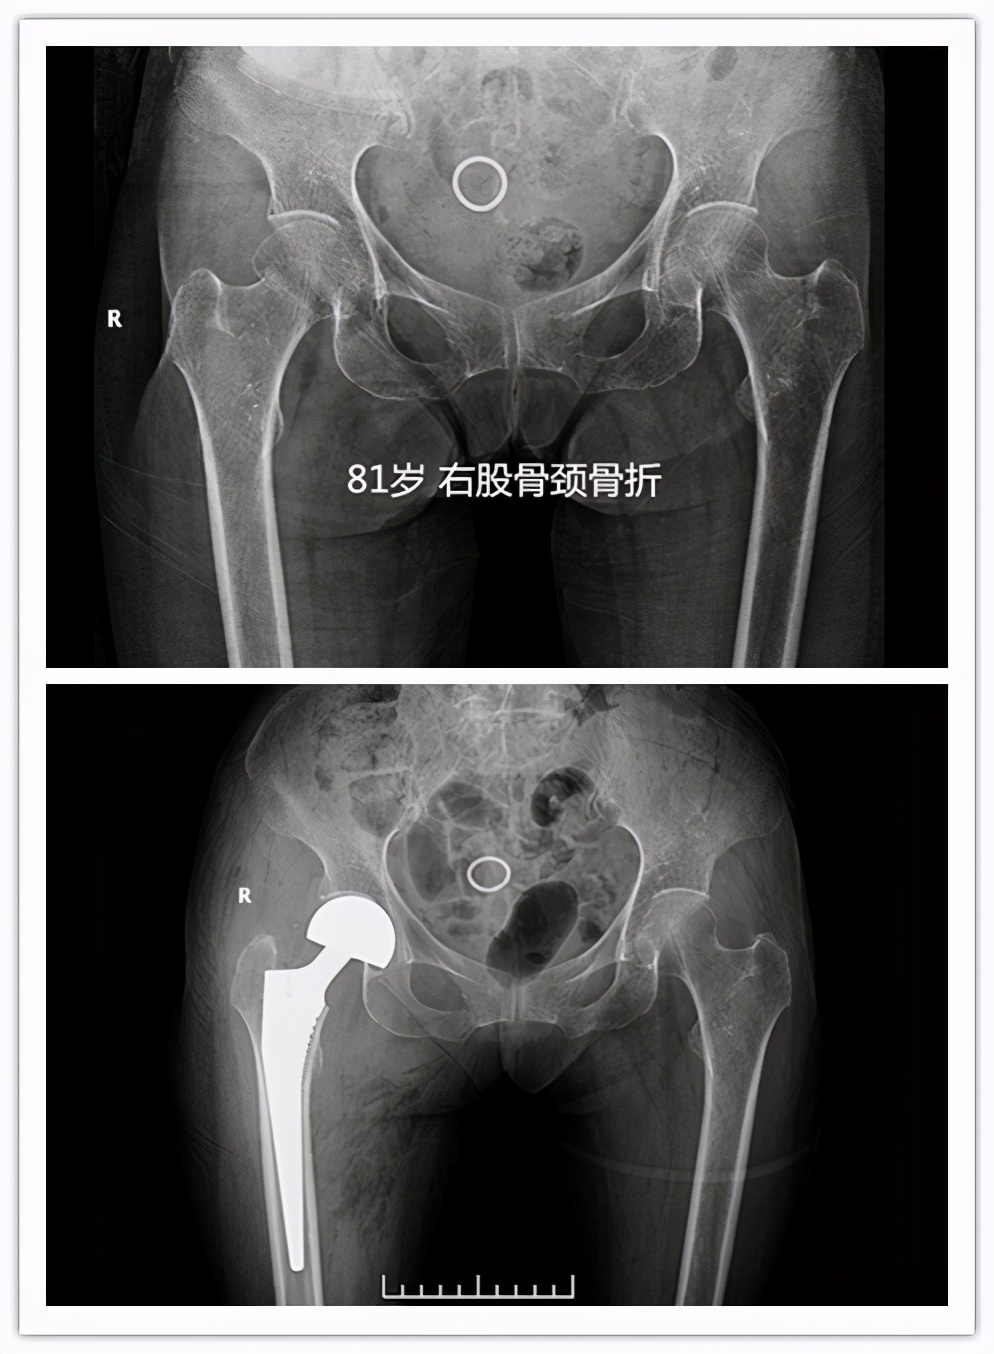

• 对于老年高龄的股骨颈骨折患者,一般可能人工股骨头置换手术,手术时间短,术后1-2日病人可早期下床活动,降低卧床并发症,提高患者生活治疗。对于粗隆间骨折,可行PFNA或者人工股骨头置换手术。

很多家属最大疑问:我们家的老人都七八十岁了,还能做手术吗?其实跌倒后出现髋部骨折多大出现于老年高龄患者,近两年我们科室做的因股骨颈骨折行人工股骨头置换手术最大年龄为 99岁 ,老人家术后2日扶助行器下床活动。 所以老人是否能耐受手术,不能只看年龄 ,需要请医师进一步进行术前评估。通过手术治疗,病人可尽早离开床,尽快恢复日常生活,提高患者生活质量,降低死亡率。